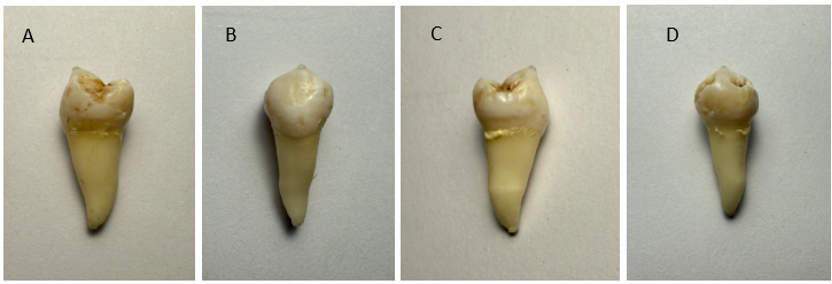

Figure 2. High-resolution optical scans of an extracted mandibular premolar (45) captured at 90-degree rotations along the long axis (root-crown) of the tooth. The STL model shown below is compared to the view of the extracted tooth in image C.